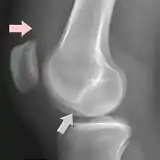

Radiograph with a deep lateral femoral notch (gray arrow) and an effusion (pink arrow)

In radiology, the deep lateral femoral notch sign is a finding on a lateral radiograph that is considered an indirect sign of a torn anterior cruciate ligament (ACL).[1][2] It is an abnormal deepening of the lateral condylopatellar sulcus from an osteochondral impaction fracture.[1][3] A depth greater than 1.5 mm is a reliable sign of a torn ACL.[1]